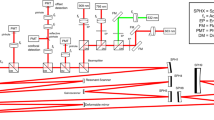

Hyperspectral imaging platform

The custom-built bench ophthalmoscope uses a 150 W xenon light source with a fast switching monochromator (Polychrome V, Till Photonics, Hillsboro, OR, USA) as a hyperspectral light source (Supplementary Fig. 1). The light source has an intensity profile which varied by wavelength (Supplementary Fig. 2). The light source was placed perpendicular to the front of the eye or the in vitro preparation thereby providing bright-field flood illumination of the specimen imaged. A semi-reflective pellicle beam splitter (BP245B1, ThorLabs, Newton, NJ, USA) directs 45% of the incident light into the rodent eye. Light from the retina is returned through diffuse reflection and passes through the pellicle again. A condensing lens focuses the image directly onto a scientific complementary metal oxide semiconductor (CMOS) chip (Andor Technology, Belfast, UK). The light source and monochromator is capable of supplying visible light for retinal imaging using 10 nm bandwidths and is able to sweep out 1 nm steps centred from 320 to 680 nm. Settling time for each step was 100 ms, so that a full spectral series of 16-bit monochromatic images at each of 361 wavebands were acquired in 36.1 s.

Hyperspectral images collected by the bench ophthalmoscope are influenced by the light output from the Polychrome V monochromator as well as the pellicle reflectance (light input arm) and transmittance (imaging arm). To correct for changes accrued in the imaging arm we divided by the pellicle transmittance profile as specified by the manufacturer; to correct for changes accrued in light input we used a power meter to measure irradiance in the plane of the pupil (therefore accounting for both the pellicle’s reflectance to the eye and spectral variations in the polychrome light source). All raw in vivo and in vitro spectra were divided by these factors (Eq. 2). See Supplementary Fig. 2 for further details.

To establish the safety of the device on the retina, a digital photometer (Model IL1700, International Light Technologies Inc., Newburyport, MA, USA) was used to compute the power density at the brightest wavelength (475 nm), which produced an output of 708.8 μW/cm2. The maximum pupil diameter measured was 2.3 mm, which approximates 30 μW of light reaching the retina. This level is considered safe based on the international electrotechnical commission 60,825 values for maximum permissible exposure42.